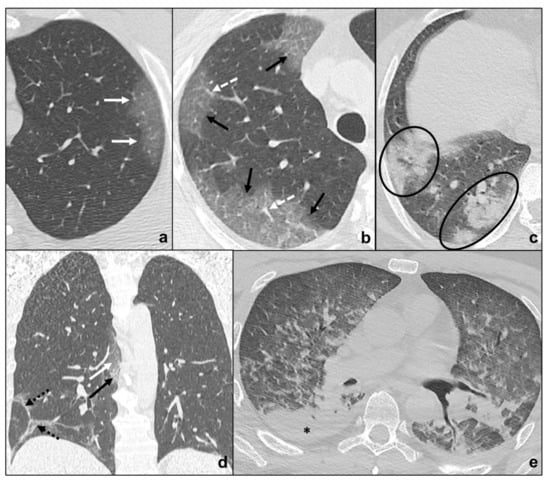

Respiratory Bronchiolitis-Associated Interstitial Lung Disease

Desquamative Interstitial Pneumonia

3.2.1. Lymphoid Interstitial Pneumonia

3.2.2. Idiopathic Pleuroparenchymal Fibroelastosis